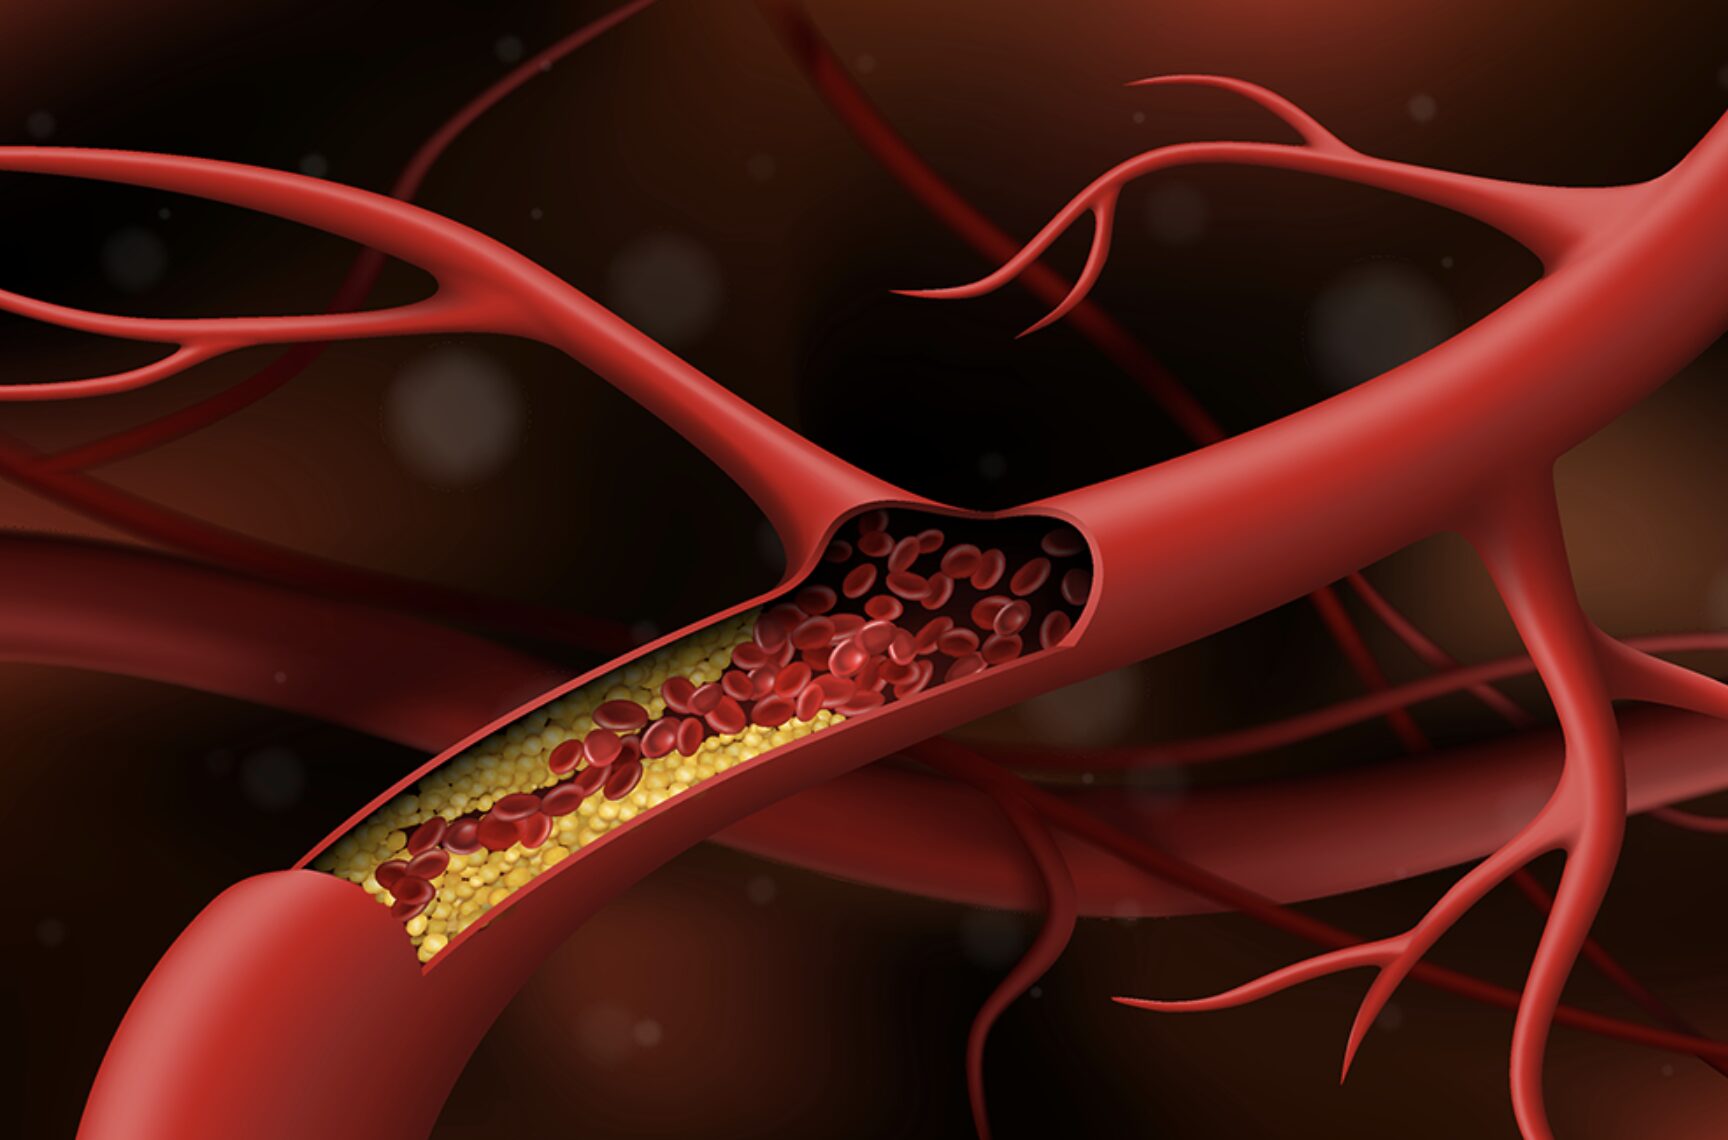

Dinh dưỡng mất cân đối: Thói quen “nuôi dưỡng” xơ vữa động mạch ở người Việt

Theo BS.CK2 Đỗ Thị Ngọc Diệp – Chủ tịch Hội Dinh dưỡng Thực phẩm TPHCM, người Việt đang ăn thiếu rau xanh và trái cây nhưng lại thừa thịt đỏ, tinh bột và chất béo bão hòa. Sự mất cân đối này không chỉ làm gia tăng rối loạn lipid máu mà còn âm thầm thúc đẩy xơ vữa động mạch, kéo theo nguy cơ nhồi máu cơ tim, đột quỵ và nhiều bệnh tim mạch nguy hiểm khác.